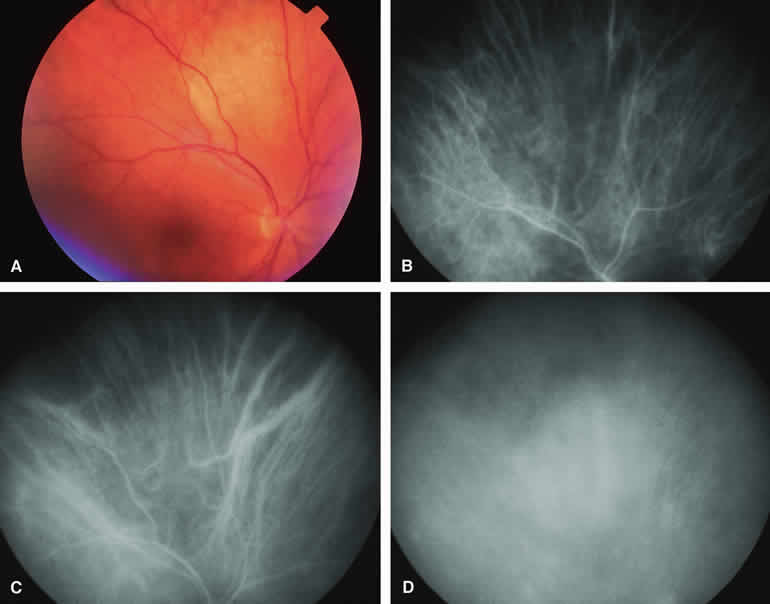

Approximately 10% to 15% of choroidal nevi are largely or completely amelanotic clinically. Fluorescein and ICG angiography of an amelanotic choroidal nevus (see Fig. 3) tend to show less prominent hypofluorescence of the lesion than they do with darkly melanotic nevi. Because of the lack of intracellular melanin pigment within the nevus cells, some large-caliber choroidal blood vessels running through the nevus may be visible in the region of the mass (see Fig. 3B and C). These choroidal blood vessels are better defined by ICG angiography than by fluorescein angiography. Amelanotic choroidal nevi often appear mildly hyperfluorescent in late-phase frames (see Fig. 3D).